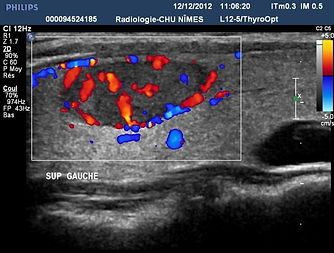

la vascularización

Valor controvertido en la literatura, la vascularización no se conserva en el sistema EU TIRADS.

La vascularización proporciona pocos argumentos diagnósticos, sin embargo en nódulos sólidos isoecoicos > 20 mm con fuerte vascularización central aumenta el riesgo de cáncer folicular, por otro lado una vasculatura periférica disminuye el riesgo.